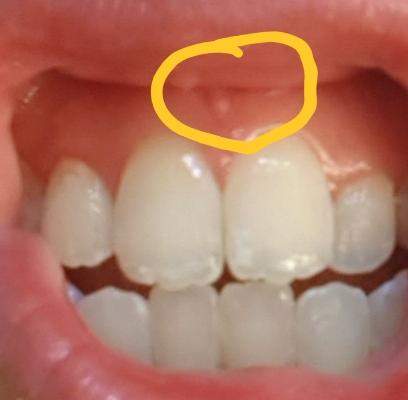

Beule am zahnfleisch ohne schmerzen. Die braucht sie dann auch. In diesen Fällen sollte man am besten zwei bis drei Tage abwarten und schauen ob sich die Situation bessert. Das sieht nach einer stark entzündeten Zahnfleischtasche aus.

Am Zahn und Zahnfleisch können viele Probleme entstehen. Die beuele ist vermutlich ein sich ausbildender abszeß der von alleine nicht besser wird auch die schmerzen werden nicht besser. Der wird die Stelle behandeln und ihr wahrscheinlich Antibiotika verschreiben.

Weitere Auslöser können sein. Eine Eiterbeuleentsteht durch die Entzündung im Knochen und am Zahn. Probleme am Zahn wie Zyste Fistel Eiter Schwellung.

Zahnentzündung apikal bedeutet dass sich die Entzündung an der Wurzelspitze befindet. Das Anschwellen vom Zahnfleisch und evt. Wenn die Wurzel am Zahn entzündet ist macht sich dies meist bemerkbar durch die Schmerzen und ein leichtes anschwellen vom Zahnfleisch.

Dehnt sie sich bis zum Kieferknochen aus heißt. Deshalb empfindet der Betroffene keine Schmerzen obwohl sich die Entzündung mit großer Wahrscheinlichkeit schon tief in den Kiefer hinein vorgearbeitet hat. Ein traumatischer Zahnunfall oder eine Verletzung.

Entweder wurde das Zahnfleisch durch mechanische Reize verletzt oder eine Infektion mit Viren Bakterien oder Pilzen ist schuld an der Entzündung. Die Beule ist unnachgiebig aber sie ist ja noch ein Kind. Diese Bakterien können einen Abszess verursachen selbst wenn die Zähne gesund und frei von Löchern sind.

Mit der richtigen Betäubung ist die Behandlung vom Zahn ohne Schmerzen. Eine Schwellung des Zahnfleisches ist ein Anzeichen für eine Entzündung.